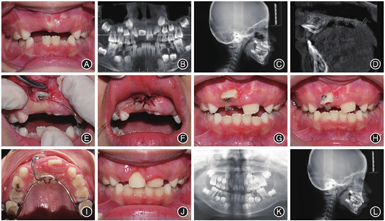

病例2女,6岁9个月,以"双侧门牙未萌,发现牙齿长歪1个月,要求检查"为主诉就诊。临床检查:替牙列,11、21均未萌,11近前庭沟处黏膜可触及牙齿隆起,54、55、64、65、74、75、84、85龋坏,双侧第一磨牙近中关系。X线片及CBCT示:21牙齿形态及萌出方向正常,牙根发育至根尖1/3,牙冠位于黏膜下,11为唇侧倒置埋伏牙,牙冠切端朝向唇侧、上方,牙根朝向腭侧、下方,牙根未发育完成,根管口呈喇叭口状,冠根比约为1∶0.5,牙根弯曲部分在根中1/3,弯曲度约为50°。矫治过程:采用外科开窗联合正畸牵引进行治疗。采用改良Nance托进行埋伏倒置中切牙的初期牵引,以增强支抗,克服牙齿在牙槽骨内的旋转移动阻力,采用闭合式牵引,即局麻下翻瓣,去除覆盖在埋伏牙牙冠上的牙槽骨,保留完整的唇侧黏骨膜,暴露牙冠后,将附有长结扎丝的舌侧扣粘接于埋伏牙牙冠舌面靠近切端,使牵引力方向与牙长轴尽量呈90°,结扎丝末端从复位瓣下方延伸至接近牙槽嵴顶引出,原位缝合牙龈瓣。牵引初期通过扭紧结扎丝加力,待牙冠暴露后换用橡皮链加力,牵引力均控制在60 g以下,每2 ~ 3周复诊加力。约4.5个月牙齿唇倾度基本正常,牙冠暴露约1/2时粘接托槽,利用2 × 4固定矫治技术进一步排齐牙齿。患者口腔卫生不佳,治疗中牙龈炎症明显,暂停加力2周,每次复诊进行龈上洁治及口腔卫生宣教。矫治时长为6.5个月,矫治结束时上切牙牙龈红肿,21牙龈肿胀明显,覆盖牙冠近1/2,嘱定期复查,采用Hawleys改良保持器进行保持(图2)。

方移动;I:上颌改良Nance托;J:治疗后口内像;K:治疗后全颌曲面断层片;L:治疗后头颅侧位片

方移动;I:上颌改良Nance托;J:治疗后口内像;K:治疗后全颌曲面断层片;L:治疗后头颅侧位片病例3男,8岁3个月,以"左侧中切牙未萌,要求检查"为主诉就诊。临床检查:替牙列,11、12、22已萌,21未萌,11、22向缺隙处倾斜、缺牙间隙变小、上中线左偏,前牙浅覆